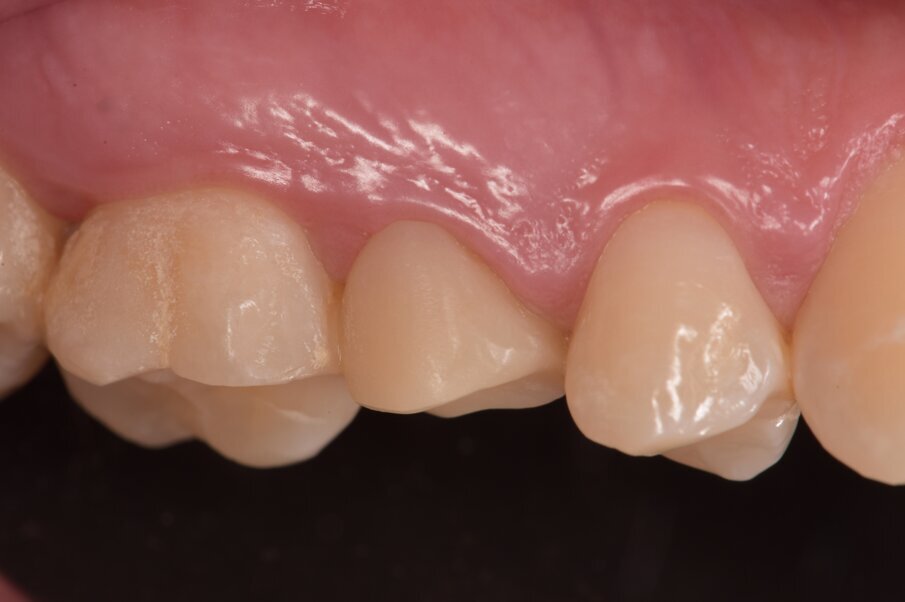

Inoltre l’analisi del progetto coronale scomposto dal moncone e dagli elementi limitrofi esalta quegli aspetti anatomici personalizzabili (Figg. 14, 15). Questo tipo di procedure digitali sono in grado di ottimizzare i tempi clinici favorendo una comunicazione più efficace e fluida. La quasi totalità dei restauri singoli non prevede delle prove protesiche intermedie, pertanto nella seduta successiva all’impronta si esegue la valutazione dei valori gnatologici di centrica e di svincolo, oltre alla verifica dei parametri estetici e biomimetici (Figg. 16, 17). Si ottimizzano altresì il profilo emergente e il rispetto dell’architettura mucogengivale armonizzandola con i denti naturali limitrofi (Fig. 6). Ad un anno siamo soliti effettuare un controllo radiografico che verrà confrontata al controllo fatto in giornata per la valutazione della presenza di cemento oltre la corona (Fig. 18).

Fig. 6_Il bianco/nero della foto esalta le forme e la mimesi anatomica delle corone e dei tessuti.